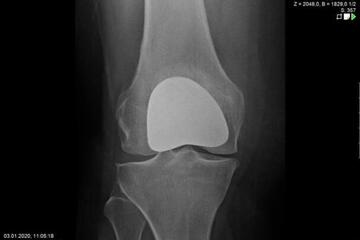

Endoprosthetics of the knee joint is an effective procedure for the treatment of symptomatic advanced wear and tear of the knee joint (gonarthrosis). If the X-ray shows a complete loss of joint space width under load, the complaints persist for more than 6 months, and the conservative therapy options have been exhausted, there is probably an indication for treatment with an artificial joint replacement (endoprosthesis). It must then be clarified which type of prosthesis is required, because today we have a large number of implants available. We distinguish between partial joints and full prostheses, and in the case of full prostheses we again distinguish between the degree of coupling of the prosthesis. If only parts of the joint are affected, only these have to be replaced and partial joints can be used. The so-called sled prostheses on the inner and outer side of the knee joint, as well as the sliding bearing replacement for problems on the kneecap, have both proven themselves effective. With full prostheses, we again differentiate between the degree of coupling of the prosthesis. Anterior and posterior cruciate ligament-supporting prostheses (surface replacement) partially coupled implants that support the inner and outer ligaments and coupled implants for complete loss of knee ligament and capsular function are used. Partially and fully coupled prostheses usually have to be inserted with stem components.